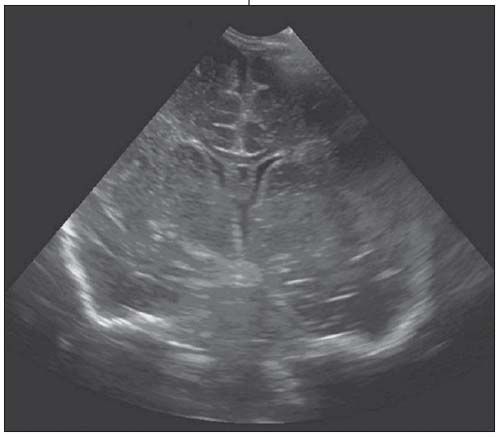

Figure 2 – An ultrasonogram obtained 7 days later demonstrates resolution of the hydrocephalus and reabsorption of the linear intraventricular strands.

On day 2 of hospitalization, a cranial ultrasonogram revealed hydrocephalus, with echogenic ependyma of the lateral ventricles, related to ventriculitis (Figure 1). Linear synechiae noted within the ventricles were characteristic of inflammation. The 3rd and 4th ventricles were normal. The findings represented a noncommunicating hydrocephalus at the level of the Monro foramen. A week later, a follow-up ultrasonogram showed resolution of the hydrocephalus and reabsorption of the intraventricular echogenic strands (Figure 2); there was no evidence of a focal brain lesion. A contrast-enhanced CT scan on day 17 revealed enhancement of the ependymal lining of the lateral ventricles with no hydrocephalus (Figure 3). Slight cisternal enlargement at the left lateral cerebral convexity and right frontal region, consistent with sympathetic effusion (exudative effusion caused by disease in nearby structure), was also present. The parenchyma was normal.